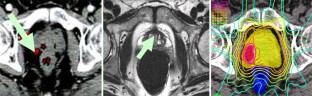

Abb. 2